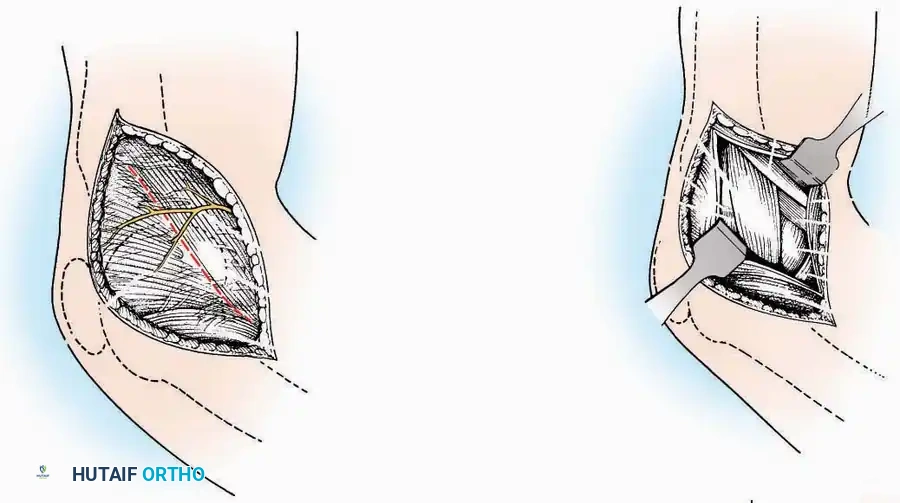

Medial Approach

Indications: Fixation of sustentaculum tali fractures, medial process fractures, or excision of medial tarsal coalitions.

Positioning: Supine with the hip externally rotated and knee flexed (figure-of-four position).

Surgical Technique:

* Incision: Begin 2.5 cm anterior and 4 cm inferior to the medial malleolus. Carry it posteriorly along the medial surface of the foot toward the Achilles tendon.

* Superficial Dissection: Divide the fat and fascia to define the inferior margin of the abductor hallucis muscle.

* Deep Dissection: Mobilize the abductor hallucis muscle belly and retract it dorsally to expose the medial and inferomedial aspects of the calcaneal body.

* Plantar Exposure: Continue distally by dividing the plantar aponeurosis and the muscular attachments to the calcaneus, or strip them subperiosteally with an osteotome.

* Neurovascular Warning: Meticulously identify and protect the medial calcaneal nerve and the nerve to the abductor digiti minimi (first branch of the lateral plantar nerve), which are highly vulnerable during inferior retraction.